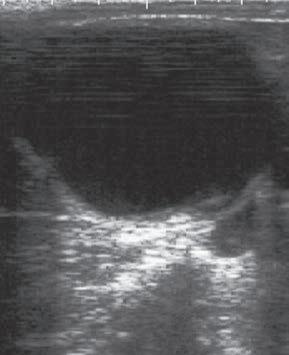

• Anecogénico o Aneoico: Se emplea para describir los tejidos que permiten el paso de todos los ultrasonidos hacia tejidos más profundos, no reflejando ningún sonido hacia el transductor. Estas superficies se verán de color negro en la pantalla y suelen corresponderse con estructuras con contenido líquido.

• Sombra Acústica: Se conoce con este nombre a una zona de menor brillo que se produce como consecuencia de que llega una menor cantidad de ondas de ultrasonido a la zona por haber sido reflejados en las capas más superficiales.

• Refuerzo posterior Este artefacto se basa en que los sonidos, después de atravesar un líquido homogéneo, su atenuación es menor que en las superficies circundantes, por lo que observaremos una zona más ecogénica.

La exploración ecográfica de los ovarios nos permite diferenciar fácilmente las estructuras fisiológicas presentes. Así veremos que los folículos aparecen en la imagen como estructuras más o menos circulares y negras, que no suelen hacer prominencia en la superficie del ovario. Por contra, las estructuras luteínicas presentarán una imagen de un tono gris oscuro, con una forma circular y en la mayor parte de los casos apreciaremos una cabeza, más o menos evidente, que hace una prominencia en la superficie ovárica. En el interior de esta estructura luteínica puede verse una pequeña cavidad con líquido (anecogénica) o bien una especie de banda blanca (hiperecogénica) que atraviesa el cuerpo lúteo de un lado a otro (travécula).

Muchos cuerpos lúteos en los 2-3 primeros días después de la ovulación pueden presentar una imagen ecográfica similar a las que se muestran a continuación. La parte central es hiperecogénica y se corresponde con el coágulo en proceso de transformación, tal como se puede ver en la primera imagen de la serie.